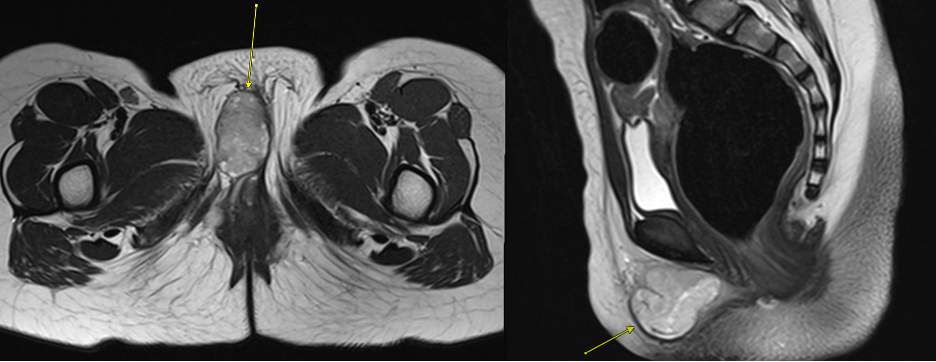

Diagnostic and laboratory testing. Contrast-enhanced MRI of the pelvis was obtained for better lesion characterization and surgical planning. MRI demonstrated a well-circumscribed, predominantly solid lesion with some cystic components, measuring 2.8 x 2.0 x 2.6 cm in the right labial region. The mass was homogenously hypointense on T1-weighted images and intermediate intensity T2-weighted images (Figure 1). Post-contrast imaging revealed heterogeneous, predominantly peripheral enhancement (Figure 2). Diffusion-weighted imaging (DWI) suggested high cellularity with diffuse diffusion restriction (Figure 3). T1 imaging suggested the absence of microscopic fat, hemorrhage, or calcifications (Figures 1 and 4). It appeared confined to the labia without deep pelvic infiltration. There were no suspicious satellite lesions or lymphadenopathy in imaging.

Figure 2. Pre-contrast axial T2-weighted MR image of the pelvis demonstrating a well-circumscribed, intermediate intensity lesion (arrow) within the right labia.

Figure 3. Pre-contrast axial T1-weighted Dixon "fat only" MR image demonstrating absence of fat signal within the right labial mass (arrow).

Figure 4. Axial diffusion-weighted imaging (DWI; left) and apparent diffusion coefficient (ADC; right) images show diffusion restriction within the mass (arrow). This finding suggests high cellularity and raises concern for malignancy.